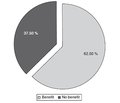

Рівень ацетилхолінестерази в сироватці крові до та після резекції в пацієнтів із хворобою Гіршпрунга

Illona Okvita Wiyogo (1), IGB Adria Hariastawa (1, 2), Munawaroh Fitriah (1, 2), Fendy Matulatan (1, 2)

(1) - Universitas Airlangga, Surabaya, East Java, Indonesia

(2) - Dr. Soetomo General Academic Hospital, Surabaya, Indonesia